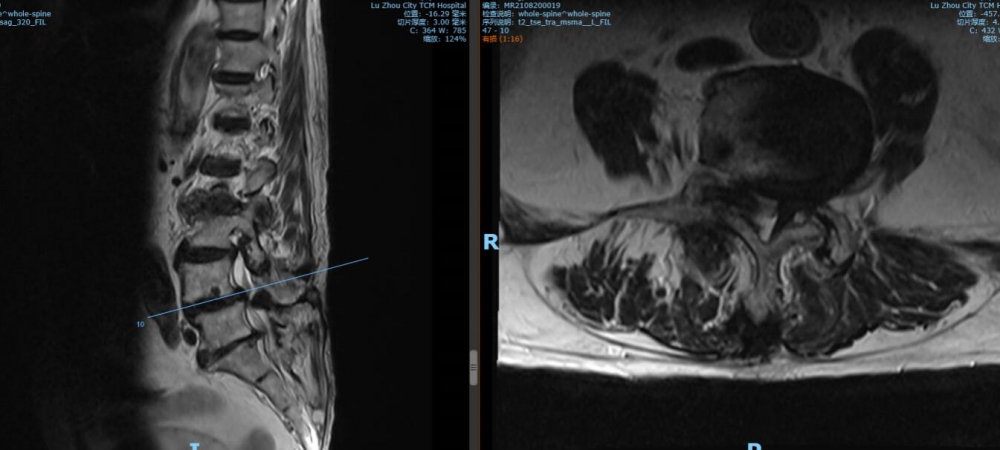

腰4 5椎間盤CT

腰4 5椎間盤MRI

腰5 骶1椎間盤CT

腰5 骶1椎間盤MRI

瀘州市中醫(yī)醫(yī)院骨傷二科主治中醫(yī)師胡建超介紹,李謹行老人患有腰椎管狹窄癥 、腰4椎I°滑脫 、脊柱退行性側(cè)彎畸形 、冠狀動脈粥樣硬化性心臟病、心律失常、高血壓2級等17種疾病,同時處于慢性阻塞性肺病加重期和腦梗塞恢復期。92歲、全身多種疾病,隨時可能會有突發(fā)情況,要做這樣一個大手術(shù),對醫(yī)生和患者來說,無疑都是一個巨大的挑戰(zhàn)。